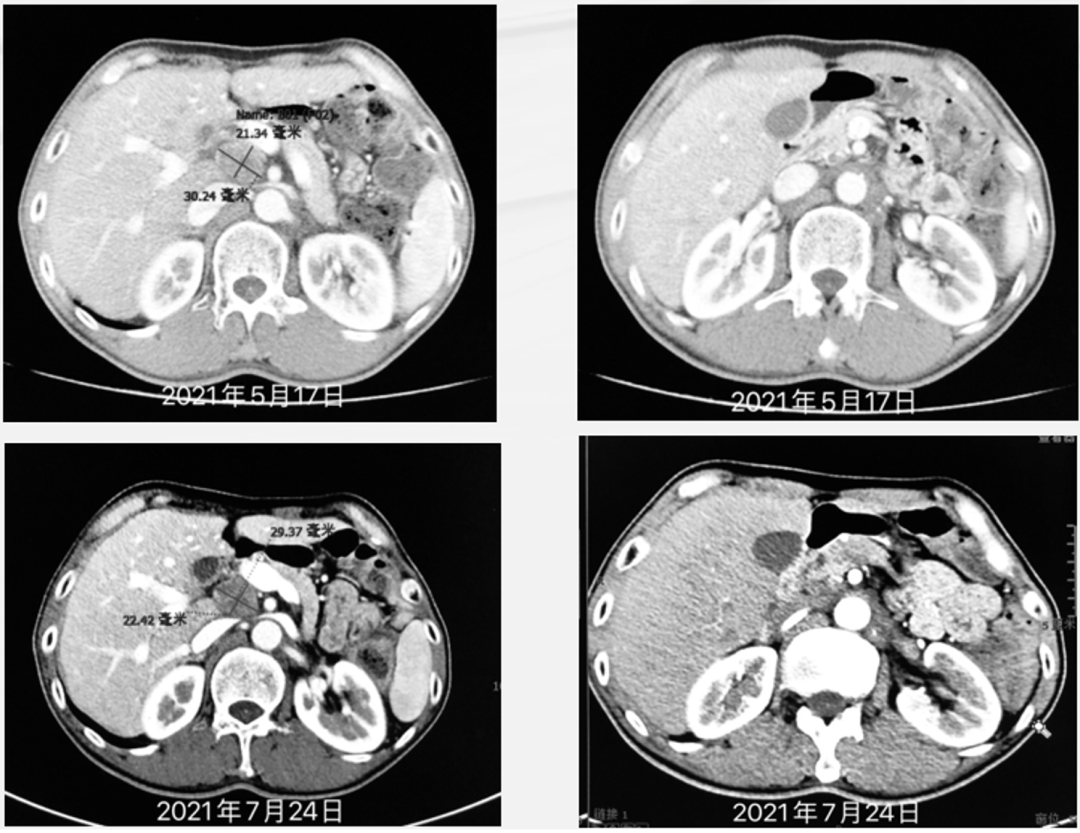

对于一线治疗进展的晚期胃癌患者而言,二线治疗依然是以化疗为主,但临床疗效欠佳,PFS仅2-3个月。在此背景下,抗血管生成药物的出现丰富了该类患者的治疗选择,此后,随着实践经验不断积累,抗血管药物又被纳入《中国临床肿瘤学会(CSCO)胃癌诊疗指南》二线治疗推荐,地位也得到进一步稳固。 那么抗血管生成药物Apatinib/ target=_blank class=infotextkey>阿帕替尼联合化疗究竟可为晚期胃癌患者带来怎样的获益?下面分享由山西省肿瘤医院常红霞教授带来的Apatinib/ target=_blank class=infotextkey>阿帕替尼二线治疗晚期胃癌的精彩病例,患者总生存期显著延长,且存活至今,获益明显,以下见详细资料: 常红霞 教授 山西省肿瘤医院消化内科 主任医师,医学硕士 中国抗癌协会多原发和不明原发肿瘤专业委员会常委 中国康复医学会健康伦理工作委员会常委 中国抗癌协会康复会学术指导委员会委员 中国医药教育协会盆腔肿瘤专业委员会委员 山西省抗癌协会大肠专业委员会委员 山西省抗癌协会靶向治疗专业委员会委员 基本情况 患者男,50岁。 既往史: 既往体健,2019年1月出现进食哽噎感,胃镜提示贲门腺癌,3月29日就诊于我院CT提示贲门周、小弯侧多发增大淋巴结,考虑转移; 2019年4月4日至6月21日行SOX方案术前新辅助化疗3周期; 2019年7月29日行贲门癌切除术,术后病理:贲门胃体:腺癌,中分化,溃疡型(Lauren分型:混合型),肿物大小3.5 × 1.5 × 1cm,浸润胃壁达深肌层,肿物累及食管下段,未见明确神经及脉管累犯,送检上、下切缘未见癌。网膜未见癌。淋巴结转移性癌(1/10), 病理分期:ypT2N1M0 ⅡA期。免疫组化:EBer(-),MLH1(+),PMS2(+)MSH2 (+), MSH6 (+), HER-2(0),PD-L1表达阳性,CPS评分:10。 术后行SOX方案辅助化疗2周期,末次化疗时间:2019年10月9日。 家族史:父亲因肺癌去世。 本次入院情况 患者于2020年08月初出现背困,化验肿瘤标志物提示CEA(-),AFP、CA724升高。 诊断 贲门癌术后,腹腔淋巴结转移(T2N1M1,IV期),ECOG 1分。 一线治疗 2020-09-07日至2021-01-13日应用卡瑞利珠单抗(200 mg,d1)+卡培他滨(1.5 g,bid,d1-14)+奥沙利铂(190 mg,d1)方案6周期,Q3W。 患者背困缓解,影像学检查:2020年11月17日复查CT提示腹腔及腹膜后淋巴结明显缩小。3周期后疗效评估部分缓解(PR)。 2021年3月7日复查CT提示门腔间隙淋巴结略增大,余腹腔及腹膜后淋巴结缩小。6周期后疗效评估疾病稳定(SD)。 维持治疗 卡瑞利珠单抗治疗3周期。 2021年5月初出现腹痛,AFP、CA724升高,2021年5月17日复查CT提示门腔间隙淋巴结增大。疗效评估疾病进展(PD)。 二线治疗 入组阿帕替尼+卡瑞利珠单抗及标准化疗治疗晚期胃癌二线患者的单臂、开放、多中心真实世界研究。 2021-05-24至2021-07-01期间接受阿帕替尼(250mg,qd)+卡瑞利珠单抗(200mg,d1)+多西他赛(90mg,d2)治疗3周期,Q3W。 患者腹痛缓解,影像学检查:2021年7月24日复查CT提示门腔间隙淋巴结缩小,余腹腔及腹膜后淋巴结缩小。3周期后疗效评估为SD。 随访至今(2023年12月),患者仍存活。 治疗总览 总结 本次分享的是一例贲门癌术后复发,合并腹腔淋巴结转移(T2N1M1,IV期)患者,一线治疗采用卡瑞利珠单抗+XELOX方案,3周期后患者症状缓解,转移淋巴结明显缩小,疗效评价PR,6周期后评效SD,后采用卡瑞利珠单抗维持治疗,期间患者发生腹痛、肿瘤进展,疗效评价PD。二线治疗患者入组“阿帕替尼+卡瑞利珠单抗及标准化疗治疗晚期胃癌二线患者的单臂、开放、多中心真实世界研究”,接受阿帕替尼+卡瑞利珠单抗+多西他赛治疗3周期,影像学检查示患者转移淋巴结较前缩小,疗效评价SD,且治疗可耐受,未发生严重的免疫相关不良反应。目前患者仍存活,持续接受治疗,总体状况良好。 二线治疗亟待攻坚 抗血管生成药物扮演重要角色 胃癌作为未尽之需最为显著的恶性肿瘤之一,严重威胁我国广大患者的生命健康。据2020年最新数据显示,我国胃癌发病率、死亡率均位居第三,疾病负担无比沉重。更值得注意的是,胃癌首诊晚期比例高,部分可手术患者行根治性切除术后易复发,因此,系统治疗对于延长患者总生存期、改善预后结局至关重要。然而,从用药抉择角度看,胃癌治疗选择匮乏,尤其是对于一线进展后开启二线治疗的患者,如何进一步提升生存获益是亟需深入思考的攻坚课题。 近年来,随着研究逐步深入,研究者发现血管生成是肿瘤生长转移的最基本因素,肿瘤通过诱导血管生成获得氧气和营养,从而使肿瘤得以迅速的生长并同时为肿瘤的远端转移提供转运。因此,抗血管生成治疗可有针对性抑制肿瘤新生血管,具有十足应用潜力,相关循证证据也在源源不断地实践、积累。 突破化疗困局 “双艾”联合化疗带来希望曙光 对于一线治疗进展的晚期胃癌患者而言,既往二线治疗依然是以化疗为主,但临床疗效欠佳,PFS仅2-3个月。在此背景下,抗血管生成药物的出现丰富了该类患者的治疗选择。其中,小分子酪氨酸激酶抑制剂(TKI)阿帕替尼可高度选择VEGFR-2受体,并抑制由其介导的血管生成过程,具有确切的抗肿瘤生长作用。 结合本例患者诊疗过程来看,其一线免疫联合化疗尽管初取成效,但后续发生疾病进展,二线治疗入组阿帕替尼+卡瑞利珠单抗及标准化疗治疗晚期胃癌患者的单臂、开放、多中心真实世界研究,接受阿帕替尼+卡瑞利珠单抗+多西他赛治疗3周期,后疗效评估提示SD,患者转移淋巴结较前缩小,且治疗可耐受,未发生严重的免疫相关不良反应,进一步从真实世界角度验证了靶向药物+免疫和化疗的可靠疗效。 期待随着探索的逐步深入,大型III期临床研究陆续开展,以更大样本量、更高级别证据为晚期胃癌二线治疗提供切实有效的“靶免化”新选择!